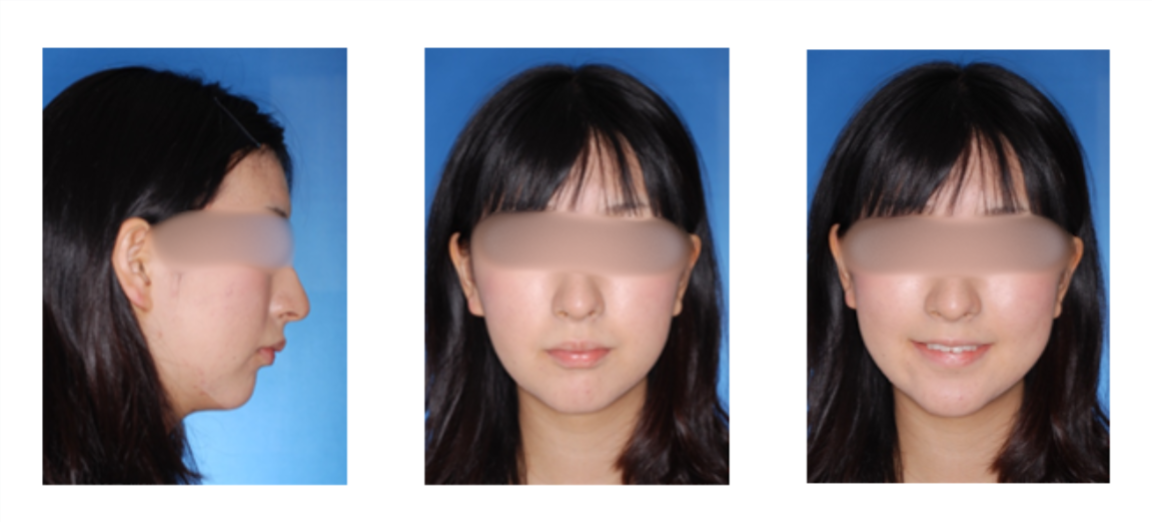

外科症例(反対咬合)の症例

初診時

治療終了時

治療終了から3年経過時

(保定開始から3年経過時)

初診

治療終了時

治療終了後から3年経過時

(保定開始時から3年経過時)

| 年齢・性別 |

20代 女性 |

| 主訴 |

咬み合わせが逆なのが気になる。 |

| 治療について |

骨格的な問題が大きいことから外科的矯正治療としました。 |

| 治療期間 |

2年9ヶ月 |

| 治療費用 |

累計約550,000円(保険適用の治療になります。 手術費用も含んだ総額です。) |

| 治療に用いた主な装置 |

マルチブラケット装置(表側の装置)、歯科矯正用アンカースクリュー、パラタルレバーアームシステム |

| 抜歯部位 |

上顎左側第二小臼歯、右側第一小臼歯、両側第二大臼歯、下顎両側第三大臼歯を抜歯 |

| 通院回数 | 26回 |